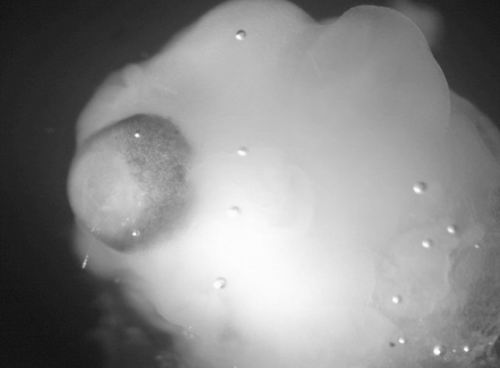

图片来源:Madeline A. Lancaster

本报讯 这个神经细胞集群——左侧有一个初级眼睛——不比一粒苹果籽大多少(如图所示)。这些神经细胞集群由胚胎干细胞发育而来,包含数量惊人的类似早期人脑的结构,其中包括视网膜组织、大脑皮层(大脑的最外层),以及脉络丛(处理脑脊髓液的腔洞)。